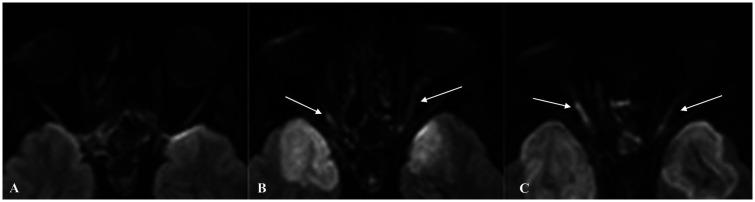

Mucormycosis is an opportunistic fungal infection involving among others the paranasal sinuses, nasal fossa and brain parenchyma. Mucor can invade the brain parenchyma by either contiguous spread from the paranasal sinuses or through vascular invasion. We report a case of fatal rhino-cerebral mucormycosis in whom cytotoxic edema at magnetic resonance diffusion-weighted imaging was symmetrically restricted to both neocortical and paleocortical primary areas of olfactory projection at earliest phase of the disease process. Shortly later tissue damage extended into the whole brain. This undescribed observation raised the hypothesis of preferential way of brain invasion by Mucor through the olfactory tract.